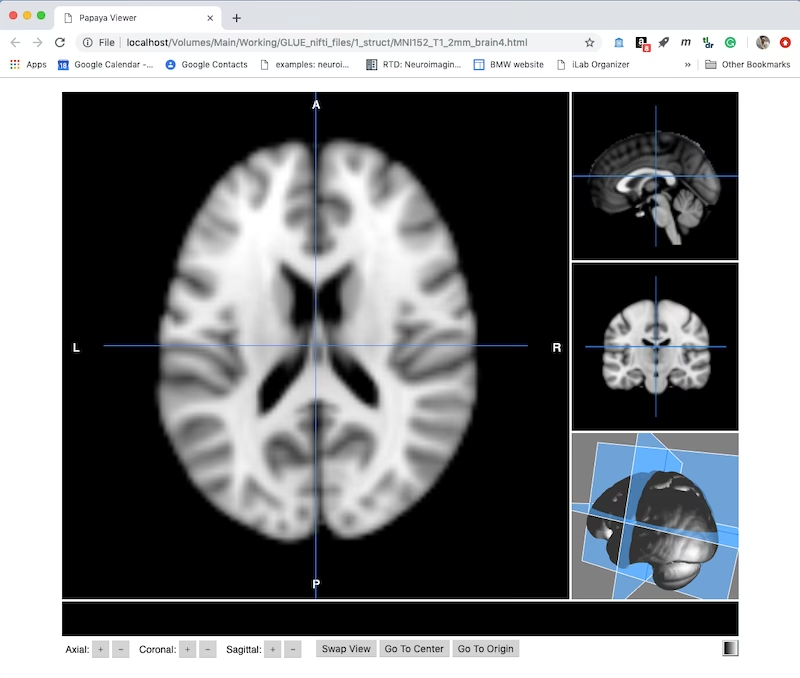

Pe scurt, Mango – prescurtarea de la Multi-image Analysis GUI – este un vizualizator avansat pentru imagini medicale de cercetare. El nu este doar un simplu program de vizualizare, ci un sistem complet care oferă instrumente sofisticate de analiză și o interfață intuitivă pentru a naviga prin volume complexe de imagini. Gândiți-vă la el ca la un microscop digital extrem de puternic, capabil să vă arate fiecare detaliu al structurilor interne, dar și să efectueze calcule și procesări complexe pe aceste date. Scopul său principal este de a facilita înțelegerea și interpretarea datelor imagistice, esențiale în domenii precum neurologia, oncologia și multe altele.

| Papaya - Browser | Firefox, Chrome, Safari, Internet Explorer | O versiune bazată pe web, care permite accesul și analiza imaginilor direct din browser, fără a necesita instalare locală. Este excelentă pentru acces rapid, partajare de date și colaborare la distanță, oferind flexibilitate maximă. |

- Redarea Suprafețelor (Surface Rendering): Mango poate crea modele interactive de suprafață 3D ale structurilor vizualizate. Aceste modele suportă plane de tăiere și suprapuneri, oferind o perspectivă tridimensională detaliată și permițând explorarea anatomică din orice unghi, crucială pentru înțelegerea relațiilor spațiale.

- Suprapunerea Imaginilor (Image Stacking): Permite suprapunerea mai multor imagini bazate pe praguri și transparență. Acest lucru este util pentru a vizualiza relația dintre diferite straturi sau tipuri de date, cum ar fi combinarea unei imagini structurale cu o hartă de activitate funcțională, oferind o imagine de ansamblu îmbunătățită.